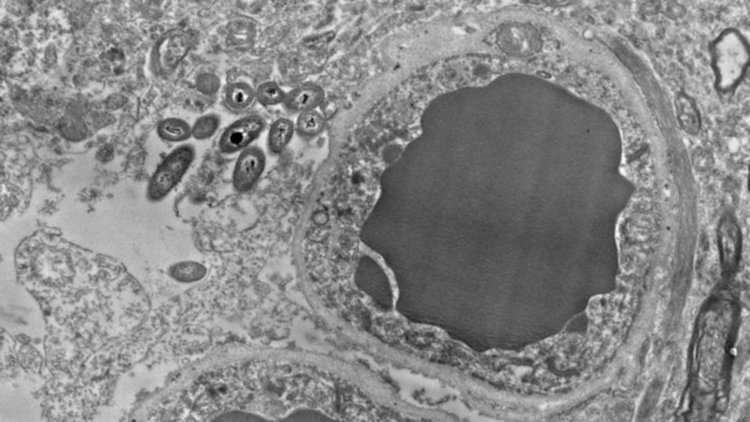

Изображение на микроскоп с висока разделителна способност, представено тази седмица на ежегодната среща на Дружеството за невронни науки, показва бактерии, които очевидно проникват и обитават клетките на здрав човешки мозък. Работата е предварителна, а авторите внимателно отбелязват, че тъканните проби са взети от трупове и биха могли да са заразени. Много от посетителите в изложбената зала, където е показан самият постер, са са развълнувани от възможността бактериите да влияят директно върху процесите в мозъка, включително може би и да причиняват на неврологични заболявания.